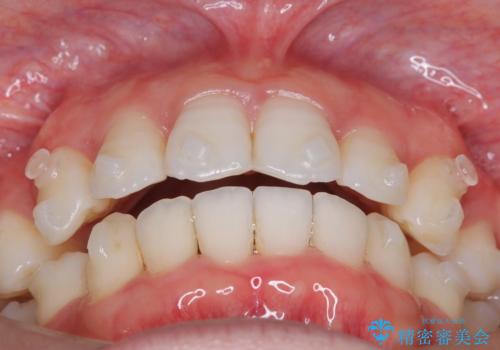

【抜歯インビザ】凸凹を綺麗になおしたい

- 前歯の凸凹を主訴に来院されました。

叢生量が多いため、抜歯が必要となるため、ワイヤー矯正をお勧めしましたが、患者さんの希望によりインビザラインで治療を開始しました。途中でワイヤーリカバリーを必要とせず終了でき患者さんには満足していただけました。